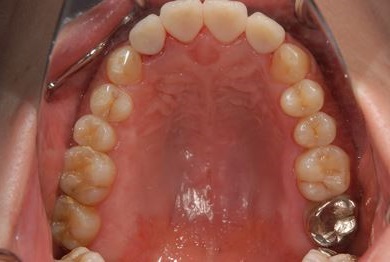

治療前

• 治療前